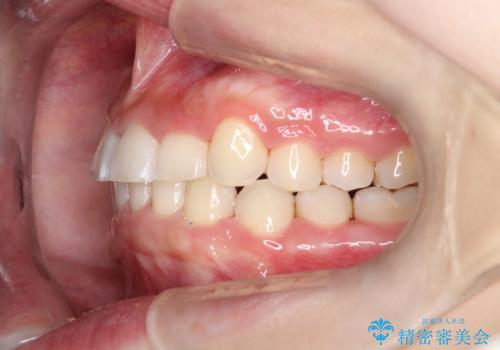

- 前歯の凸凹と深い噛み合わせを主訴に来院されました。

下の前歯が見えないほどのディープバイト症例でした。

ワイヤー矯正にて下顎前歯の圧下と臼歯部の挺出を効率的に行うことができました。

下顎前歯も綺麗に見えるようになり大変満足していただきました。